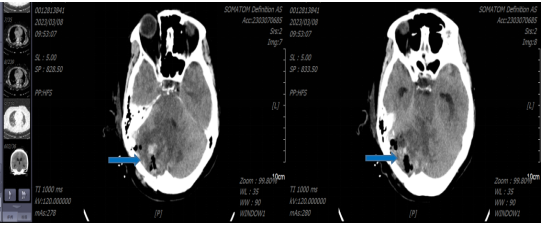

神经外科杨建雄主任、叶志其主任医师等带领神经外科一区团队经过术前病例分析,制定了详细的治疗方案,同时告知患者及家属,患者诊断考虑CPAP区巨大脑膜瘤,上顶小脑幕,内压脑干,已形成梗阻性脑积水,若不及时手术可能随时出现脑疝危及生命,且肿瘤血供丰富,肿瘤侵犯右侧横窦及乙状窦,术中出现大出血可能,做好手术备血。术中需仔细操作,减小损伤,注意保护瘤周正常脑组织,防止术后发生严重的脑水肿。在患者及家属同意的前提下,同时在省医神经外科周东主任医师的指导下,采用右侧旁正中入路切口,在显微手术下完美将肿瘤完全切除,术后复查头颅CT(蓝色箭头为残留术腔,肿瘤完全切除)。

蓝色箭头为残留术腔,肿瘤完全切除